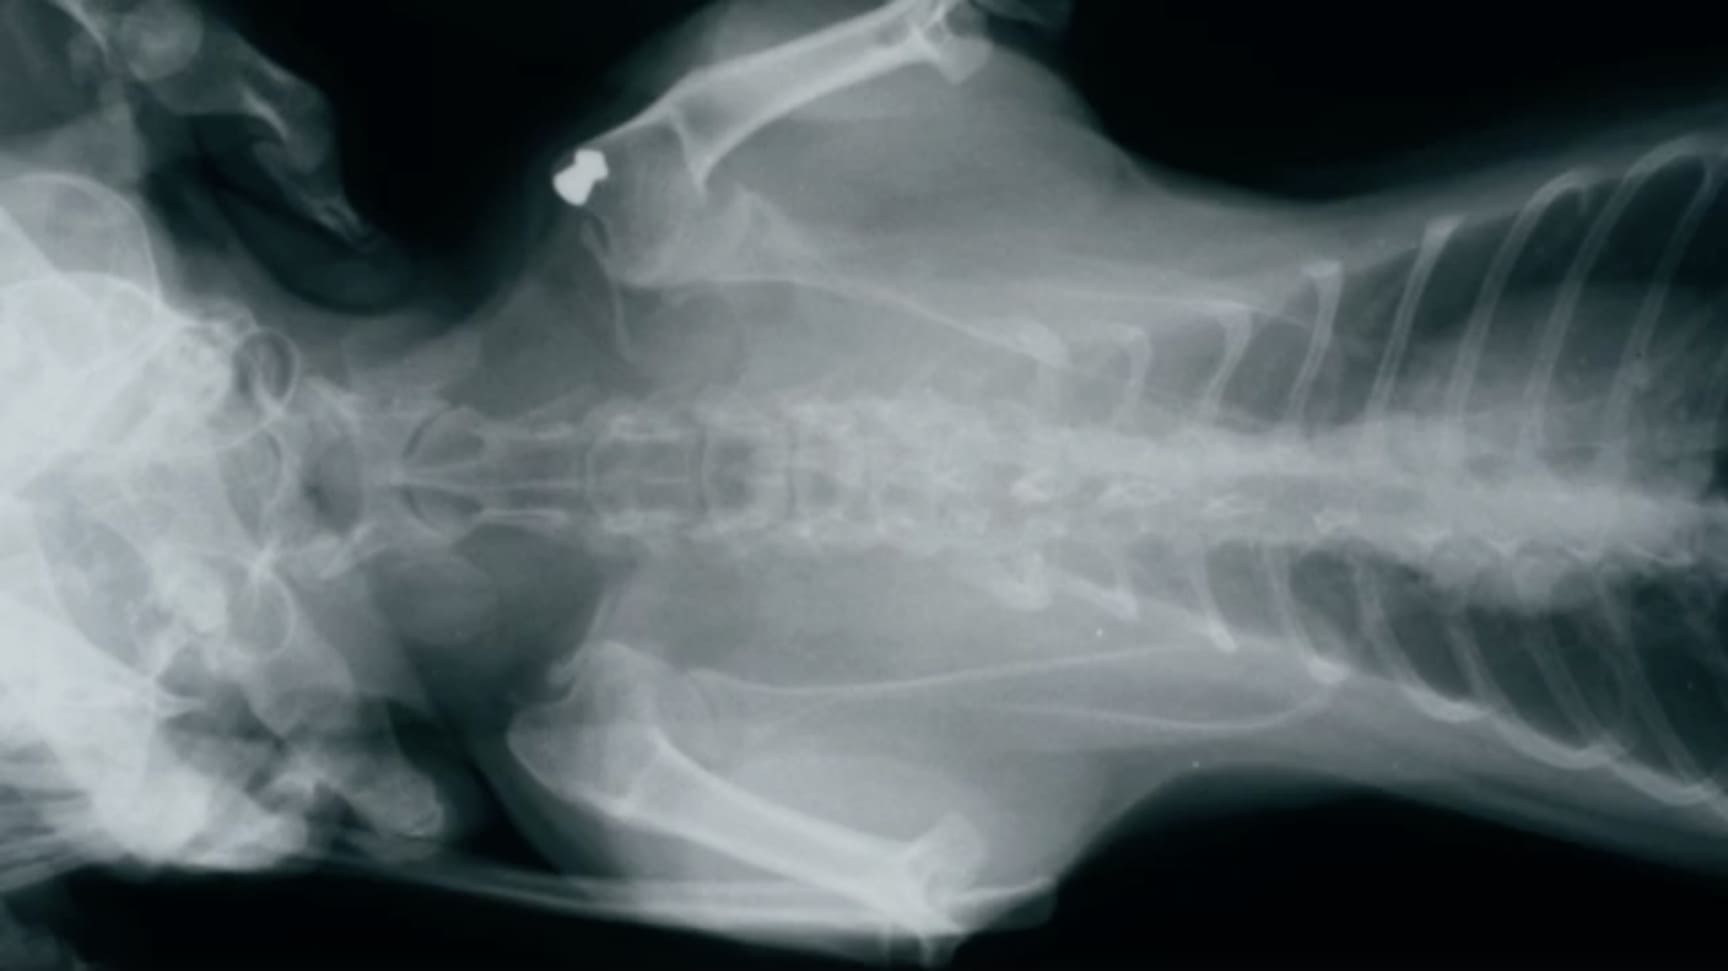

La téléradiologie vétérinaire est une technique qui permet aux cliniques vétérinaires d’envoyer des images radiologiques, de scanners ou d’IRM à distance pour les faire interpréter par des spécialistes en imagerie médicale. Cette technologie offre une solution rapide et efficace pour obtenir des diagnostics de qualité sans avoir besoin de recourir à un radiologue en interne.

Les vétérinaires nous envoient leurs examens d’imagerie médicale (radiographies, scanners, IRM).

Nos vétérinaires spécialisés analysent les images et fournissent un rapport complet avec un diagnostic détaillé.